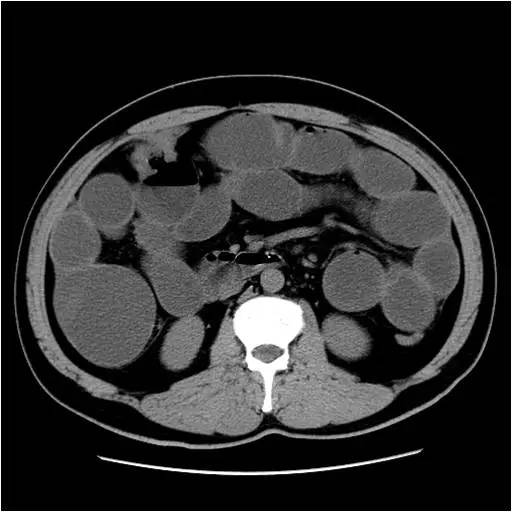

结肠肝曲肠腔内可见不规则软组织块影,呈明显强化,局部管壁增厚,管腔狭窄,浆膜面毛糙,周围脂肪间隙密度略增高,未见明显肿大淋巴结。升结肠及小肠弥漫扩张,并积液、积气,可见气液平。

诊断:结肠肝曲占位,考虑结肠癌(T3N0M0),并肠梗阻。

诊断要点:CT表现为结肠肝曲肠腔内肿块影,浆膜面毛糙,周围脂肪间隙密度增高,增强后病灶明显强化,肿块腔内生长导致肠腔狭窄进而引起肠梗阻,表明肿块由黏膜向腔内生长且浸润肠壁各层,提示为恶性占位性病变。